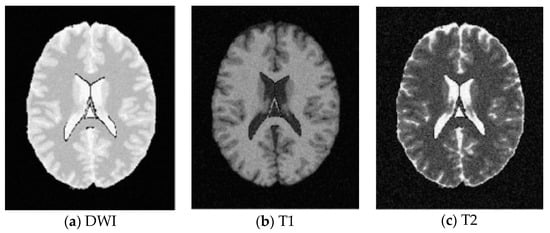

SBD: The database has DWI, T1 and T2 images of size 181 × 217 pixels. In our experiments, the classification results were quantified based on the ground truth of SBD. We added Rician noise to the analog image. In our experiments, the SNR (signal to noise ratio) values were set to 10 dB, 5 dB, 15 dB, and 20 dB, respectively. Shown in Figure 7, Figure 8, Figure 9 and Figure 10 are SBD images.

Figure 7. SBD Images with SNR = 10 dB.

Entropy 20 00964 g007